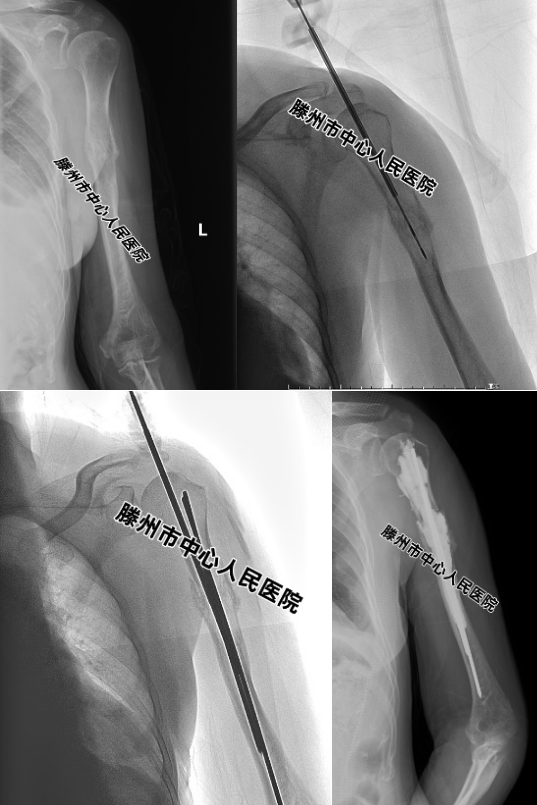

患者,女,62歲,因“咳嗽伴右上肢疼痛1個月”,在本院診斷為“肺腺癌并右肱骨轉移”。先進行放療,效果不佳,右上肢疼痛難忍,不能活動,CT、MRI及拍片檢查發現右側肱骨溶骨性轉移,骨皮質破壞明顯,隨時都有發生病理性骨折的風險。

經MDT討論,決定采用新的微創技術進行治療。張開賢主任帶領團隊,在DSA引導下,先對病變區域進行微波消融,然后置入2根克氏針,最后再注射15ml骨水泥,術后第二天疼痛消失。現患者右上肢活動正常,能從事一般家務勞動。

為此,腫瘤一科經過多年探索,創建了一種全新的微創治療術式--微波消融、骨成形術聯合經皮介入內固定(IIF),形象地稱為“鋼筋混凝土技術”。微波消融利用高溫使腫瘤發生凝固性壞死,有良好的抗腫瘤及止痛作用。消融完成以后,經皮置入數量不等的克氏針,可以進一步加強骨骼的穩定性,防止骨折的發生;最后在病變區域注射骨水泥,以達到既能快速緩解疼痛,又能提供足夠機械支撐,預防病理性骨折的目的。該微創技術可在局麻下進行;創傷小,可減少手術部位感染以及腫瘤轉移的機會;可明顯縮短臥床以及住院時間。